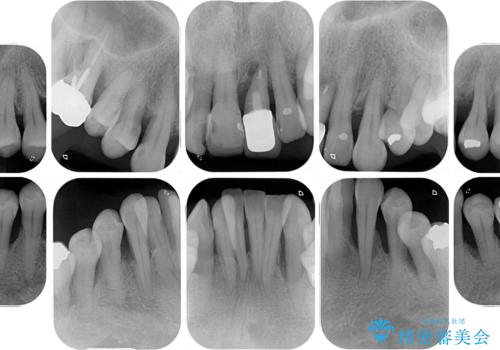

歯周病でグラグラの歯 矯正治療と歯周外科を併用した総合歯科治療

- 近医に通い続けるも、一向に不快感が改善しないとのことで来院された患者様です。

診察を行ったところ、重度歯周病の状態の上に上下の歯列が著しい叢生という状態でした。

歯周初期治療として抜歯や歯槽骨再生治療を行い、さらに歯周ポケット除去を行った後に矯正治療で歯列を整えて行くこととしました。